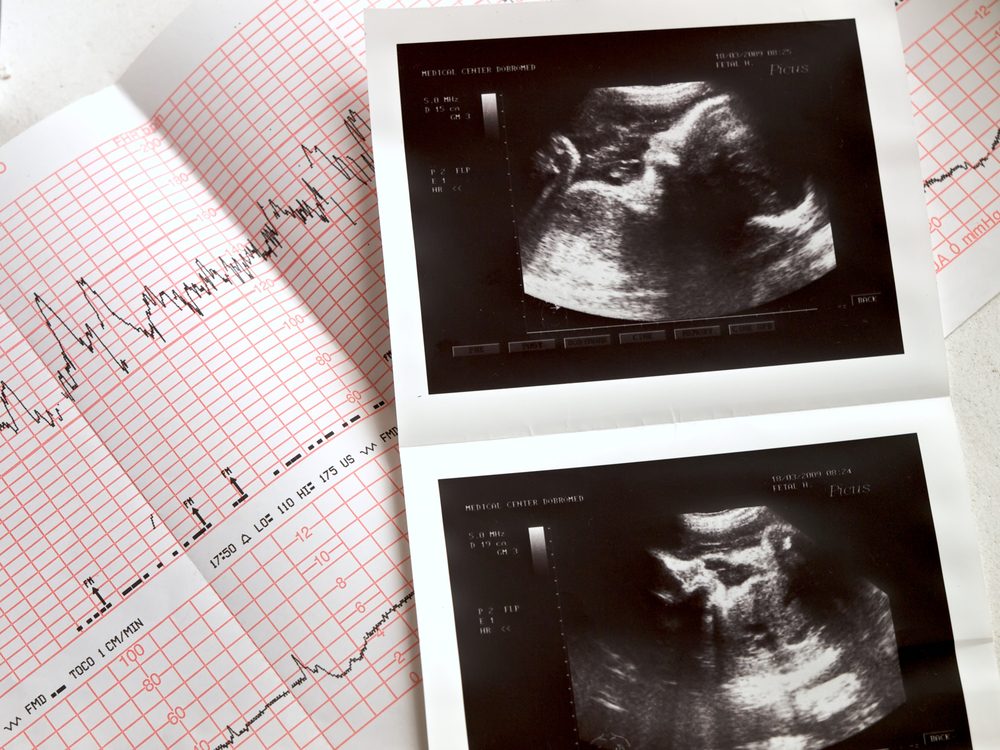

ultrasound portrait of the fetus and cardiogram results

liseykina/Shutterstock

Pregnancy

Some women will experience abdominal pain after sex during pregnancy—so if you’re experiencing it, you’ll first want to rule out pregnancy. “An ultrasound can confirm the pregnancy, and determine if the abdominal pain is due to an ectopic pregnancy; that’s when the fertilized ovum implants outside of the uterus. Another possibility is a miscarriage before 20 weeks,” says Risa Klein, CNM, certified nurse midwife. It’s easy to miss these very early pregnancy symptoms.